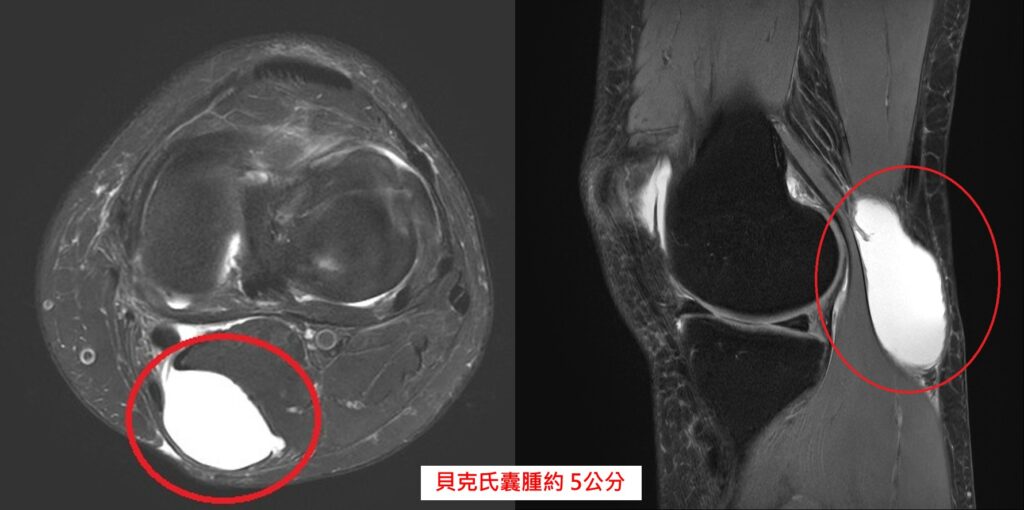

50歲女性患者近期覺得右腳後膝窩有異樣,摸起來像有顆「腫瘤」,甚至在上下樓梯、蹲跪時會出現壓迫感,嚴重時還會伴隨麻木感。求診中國醫藥大學新竹附設醫院骨科醫師陳威仁,經診斷為「貝克氏囊腫」膕窩囊腫約5公分,經醫病溝通後,病人接受微創膝關節鏡手術治療,手術約30分鐘,術後隔天即可下床活動,兩天後順利出院。

骨科醫師陳威仁表示,貝克氏囊腫常見於中高齡族群,主要還是跟退化性膝關節炎伴隨,成因是關節腔內關節液過多(膝蓋積水),過多的關節液因為膝內壓力過大經由膝關節後方的單向閥門流出,堆積在膝窩後方,形成一顆「水球」。